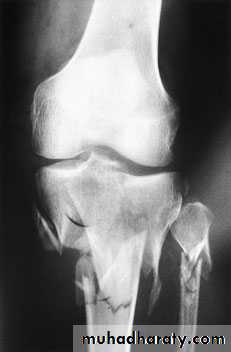

Infection.Vascular injury.